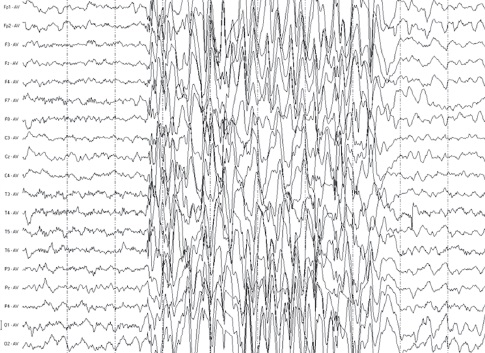

Простите, а что тот пацан должен был узнать в ЭЭГ?

Ну полосочки, и что?

Форма полос вообще никак не связана ни с какими образами внутри самой ЦНС.

ЧТО он там должен был узнать?

Это тест Роршаха что ли?

Смотрите какие разные графики по разным данным!

Ничего себе!

И что это значит????

Как такое может быть??? Это же разные графики по разным данным, как они могут быть разными?))))

99% пиздострадания, пару раз показывают какие-то графики, в конце "пришельцы" в виде дешевого cgi разростаются в виде веток деревьев во все стороны, люди бегут.